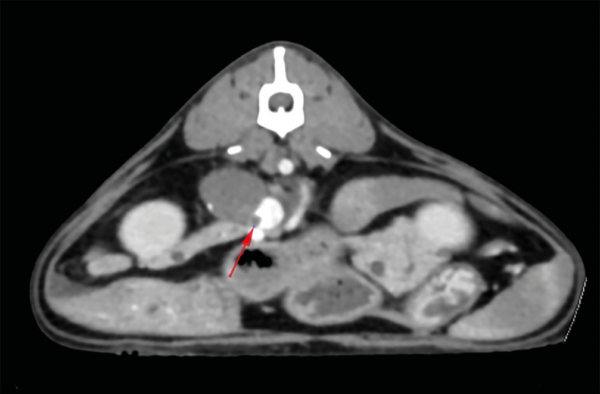

Tomografía computarizada

La prueba de elección previa a un tratamiento quirúrgico será la tomografía computarizada, ya que es una técnica superior para determinar la invasividad del tumor, identificar metástasis a distancia y planificar la cirugía (imagen 4).

En aquellos casos en los que no se realicen pruebas de imagen avanzada de tórax y abdomen, se recomienda complementar la ecografía abdominal con radiografías torácicas de tres vistas para descartar metástasis pulmonares.